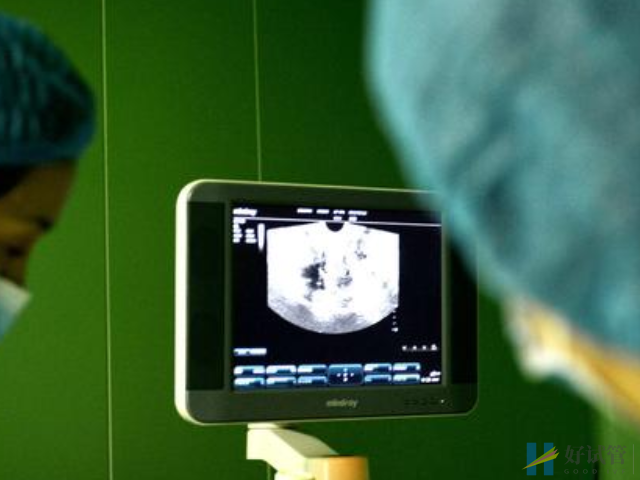

正常情况下,试管促排卵期间的卵泡都是不会出现早排的情况,因为促排期间需要定时上医院卵泡监测,看卵泡的发育情况,等长到15mm左右就会安排取卵手术,能提前排掉的几率是不高的。

促排卵期间女性是需要定期到医院进行卵泡监测的,如果说监测不及时,或者是医生不专业、医院不正规、设施设备不好的话,都是可能会导致监测结果出错。比如说卵泡明明即将成熟,但是没有及时发现,就会出现早排的情况。